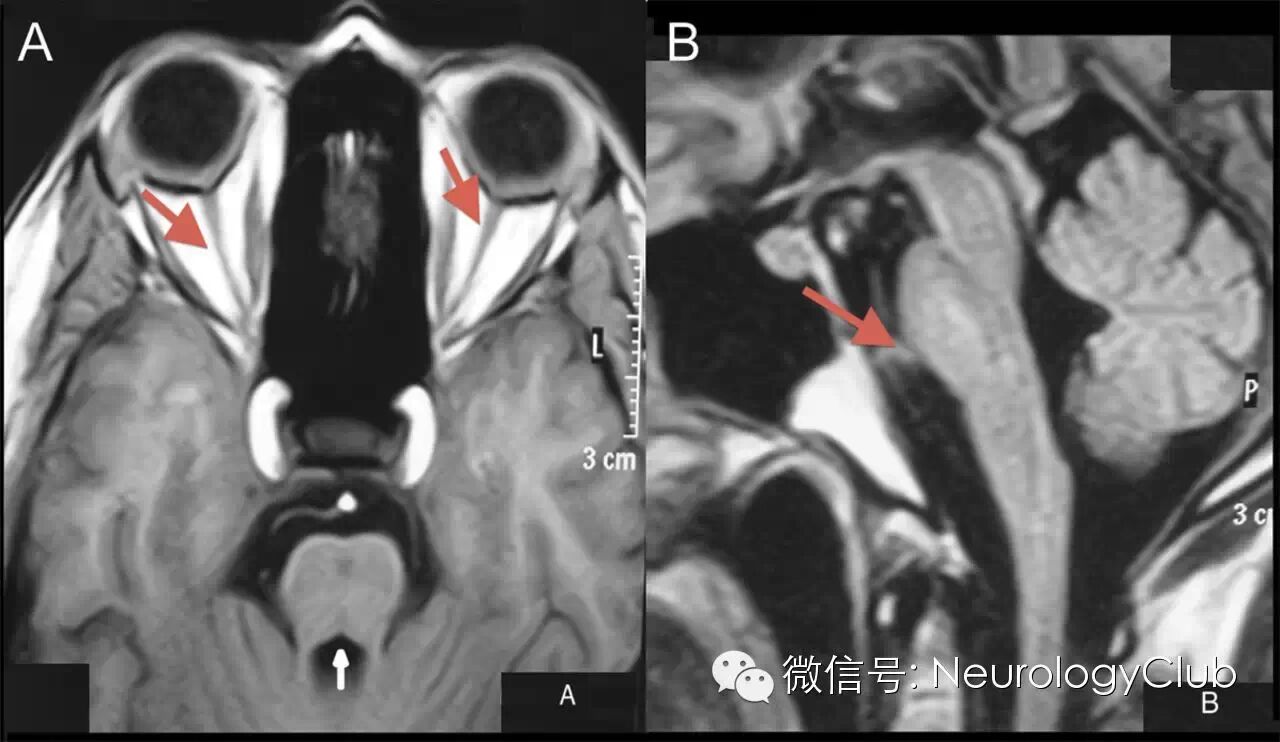

(A:水平位 FLAIR 像显示视交叉附近、双侧视束高信号;B:冠状位 T2 像可见双侧视神经萎缩。引自:Teaching NeuroImages: MRI of brain findings of Wolfram (DIDMOAD) syndrome.Neurology. 2014 Dec 9;83(24):e213-4.)

(32岁男性患者。A:双侧视神经,脑桥和小脑中脚萎缩;B:脑干(特别是脑桥)和小脑萎缩。引自:Teaching NeuroImages: a neuroendocrine rarity: Wolfram syndrome.Neurology. 2013 Nov 12;81(20):e153.)